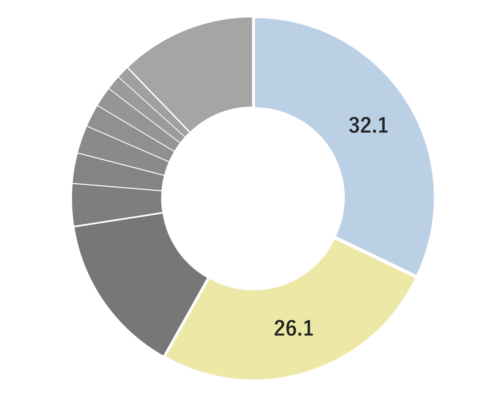

痛風性関節炎モデルマウスにおいて、1,8-シネオール投与群では炎症による腫れが濃度依存的に小さくなったことが報告されました。1)

スカトールや3-メチルブタン酸などの異臭成分を、それぞれ1,8-シネオールとともに密閉容器内で静置したところ、異臭成分の濃度が減少したことが報告されました。2)

ヒト脳毛細血管内皮細胞HBMECsにおいて、1,8-シネオール添加によりマラリア原虫が感染した赤血球の付着が減少したことが報告されました。さらに同報告において、マウスマラリアモデルにおいて脳浮腫が抑制されることが報告されました。3)

線虫モデルにおいて、1,8-シネオール投与により線虫体内の活性酸素種(ROS)レベルが低下することが報告されました。4)

マウスおよびモルモットにおいて、カルバコールによって誘発された気管支平滑筋の収縮が1,8-シネオール投与により弛緩することが報告されました。さらに同報告において、カルバコールによって誘発された気管抵抗が、1,8-シネオール投与により減少することが報告されました。5)

作業能率への影響を暗算課題の正答率の変化を指標に評価したところ、1,8-シネオールの香り呈示状態において暗算課題の正答率が高くなることが報告されました。6)